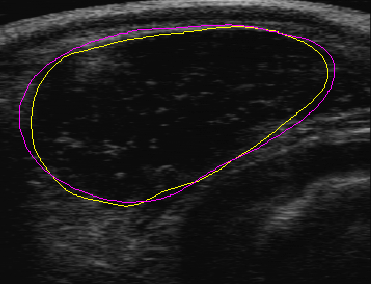

For beef, the rib eye area is an important indicator of the meat quality of an animal. Technology allows ultrasound imaging of cattle on the field, providing a potentially very useful tool for estimating the rib eye area. Deriving accurate estimates from such images is difficult, however, relying on experts who laboriously trace the outline of the rib eye and measure the enclosed area. Moreover, this process cannot be carried out in the field, and is subject to errors due to fatigue, image quality variation, and other factors.

ultrasound Gregory Randall, who spent a year at the IMA, and other IMA visitors from Universidad de la Republica in Uruguay have developed a method which enables accurate automatic in-the-field rib eye measurement. Their algorithm processes the ultrasound image data in combination with stored statistical information about rib eye shapes obtained from a bank of curves traced by experts. The method, which has been extensively tested, agrees well with the traditional expert marking and measurement method.